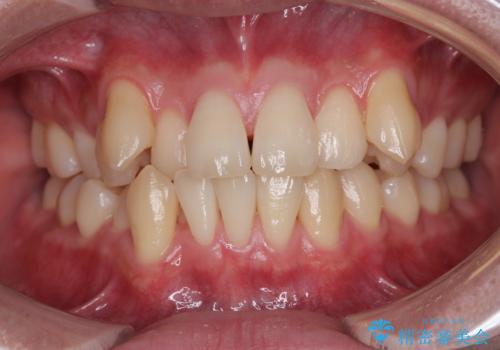

飛び出した前歯を引っ込める ワイヤー装置の非抜歯矯正